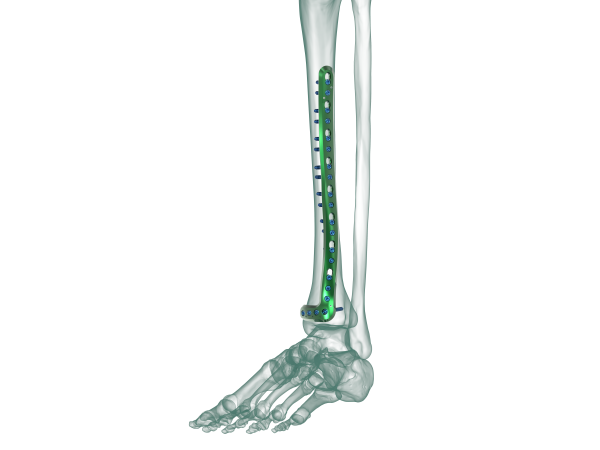

TRUE LOCK Distal Tibia Anterolateral Anatomic Plate

TRUE LOCK Distal Tibia Anterolateral Anatomic Plates are indicated for;

–  Extra-articular and simple intra-articular distal tibia fractures

–  Distal tibia fracture, percutaneous or reducible by limited arthrotomy

–  Distal tibia fracture extending into the diaphyseal area

Anatomical plate; right & left

7 different hole option between 5-17

TRUE LOCK Distal Tibia Anterolateral Anatomic Plate are made of Ti6Al4V ELI material (ASTM F136)

Anatomically shaped

Four distal head holes angle 7 degree inferiorly to capture the posterior malleolus.

Kirschner wire holes in the head, parallel to the joint, accept Kirschner wires to temporarily fix fragments and show proximity to the joint .

At the cancellous part of the bone near the joint, 4,0 mm cancellous locking screw option supports plate and screw fit well; prevents it from pull out.